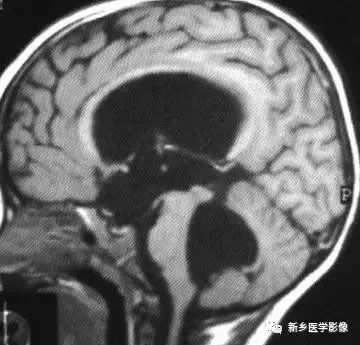

❷ 小脑扁桃体下疝畸形

又称Chiari's畸形,即小脑扁桃体下移到椎管内,延髓、四脑室延长并部分向下移位。可分为3型。各型均常有脑积水表现。

Ⅰ型:若仅有小脑扁桃体下移。扁桃体下缘低于枕大孔连线5mm以上,无脑干及四脑室改变者为Ⅰ型。

Ⅱ型:除小脑扁桃体下移外,同时有四脑室部分或全部降入枕大孔以下者为pⅡ型。

Ⅲ型:全小脑及四脑疝入枕大孔以下者为Ⅲ型。